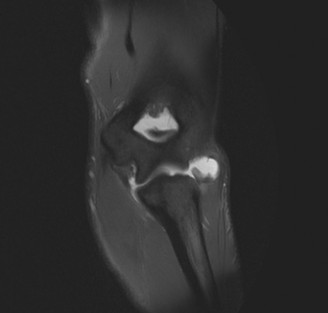

A 21-year-old, right-hand-dominant, collegiate pitcher presents to the office with elbow pain and loss of vel…